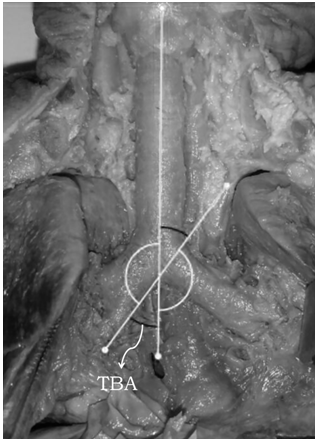

The anterior region of the neck and thorax of each fetus was opened through a midline incision from the upper edge of the thyroid cartilage to the level of the middle third of the thorax. In this way, they were exposed and dissected to the naked eye: the trachea, its bifurcation and the right and left main bronchi. The tracheobronchial angles (TBA), right (TBAr) and left (TBAl) were evaluated in situ, through the acquisition of images, from which, using the Angulus software, digital analyzes were performed (Figure 2). Measurement values in degrees and corresponded to TBArTBAl formed by passing two axes: one vertical, the point of bifurcation of the trachea and the other by the lower edge of the corresponding main bronchus. The TBA was also calculated, which corresponds to the intersection between the lower edges of the main bronchi. The values found were tabulated and analyzed using the following statistical tests: Mann-Whitney, Kruskal-Wallis, ANOVA, and Spearman correlation. All variables were compared with gestational age in order to verify if there is an increase in angles according to age, as well as their correlation with gender. A significance level of p<0.05 was also considered for the statistical tests used.

Figure 2 Right tracheobronchial angle, represented by TBA, measured using ANGULUS software.